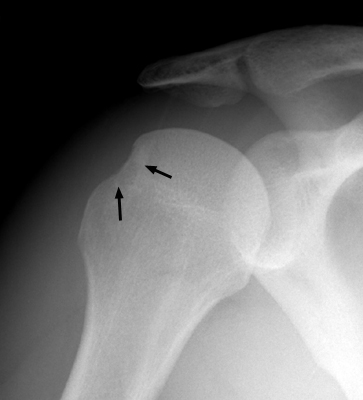

Hill-Sachs Sign

s/p anterior shoulder dislocation

Frontal film of the right shoulder which reveals a defect of the posterolateral aspect of the humeral head, consistent with a Hill-Sachs deformity. The Hill-Sachs sign represents deformity of the superior, posterior border of the humeral head and is typically a result of impaction of the anterior inferior surface of the glenoid labrum on the posterolateral aspect of the humeral head during dislocation.